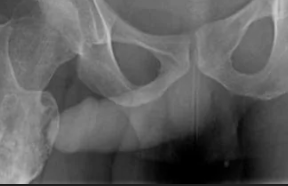

IMG20251208112948.jpg

Где пиздецома?

>>327474821

Пневмония в нижнем сегменте.

Ну или тубер

>>327475007

Там еще жижа и плеврит